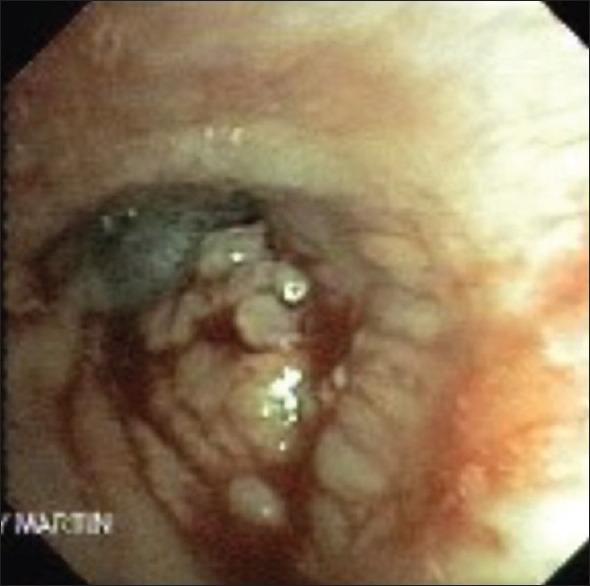

Pulmonary lymphoproliferative neoplasms are rare lung tumors and account for <1% of all lung tumors. Among them, primary pulmonary lymphomas (PPL) constitute the majority, which include Non-Hodgkin's lymphoma (NHL) that comprise of mucosa-associated lymphoid tissue lymphoma, diffuse large B-cell lymphomas and other rare types of NHL and lymphomatoid granulomatosis. HL, which arises secondary to contiguous spread from the mediastinum, is the rarest type of PPL. Other entities described within the umbrella of pulmonary lymphoproliferative neoplasms include pleural lymphomas and posttransplant lymphoproliferative disorders (PTLD) - which occurs in the poststem cell and organ transplant patients. These neoplasms although rare, have a favorable prognosis, which does not depend on disease resectability. Moreover, with its nonspecific presentation, diagnosis is challenging, which often leads to delayed diagnosis or misdiagnosis in many cases. Therefore, knowledge of this entity is important for the practicing pulmonologist. This review article aims to describe the clinical presentation, diagnosis and management of primarily the entities within PPL, as well as pleural lymphomas and PTLD.

肺淋巴增殖性肿瘤是罕见的肺部肿瘤,占所有肺部肿瘤的比例不到1%。其中,原发性肺淋巴瘤(PPL)占大多数,包括非霍奇金淋巴瘤(NHL),后者由黏膜相关淋巴组织淋巴瘤、弥漫性大B细胞淋巴瘤以及其他罕见类型的NHL和淋巴瘤样肉芽肿组成。HL是PPL中最罕见的类型,它继发于纵隔的连续性扩散。肺淋巴增殖性肿瘤范畴内描述的其他实体包括胸膜淋巴瘤和移植后淋巴增殖性疾病(PTLD)——发生于干细胞和器官移植后的患者。这些肿瘤虽然罕见,但预后良好,其预后并不取决于疾病的可切除性。此外,由于其表现不具有特异性,诊断具有挑战性,这在许多情况下常常导致诊断延迟或误诊。因此,了解这一实体对执业肺科医生很重要。这篇综述文章旨在描述主要是PPL内的实体以及胸膜淋巴瘤和PTLD的临床表现、诊断和管理。